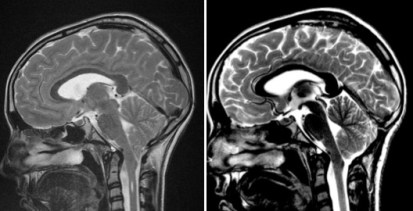

le traitement de l’hydrocéphalie

c’est la première chose à faire s’il les ventricules sont larges et que le plancher du 3ème ventricule est abaissé. cette décision est d’autant plus justifiée qu’il existe un problème hydraulique comme une syringomyélie. on réalise en première intention une ventriculo-cisternostomie endoscopique.

c’est la surveillance ultérieure, clinique et radiologique, qui fera décider, ou non, d’une geste de seconde intention sur la charnière cranio-cervicale.